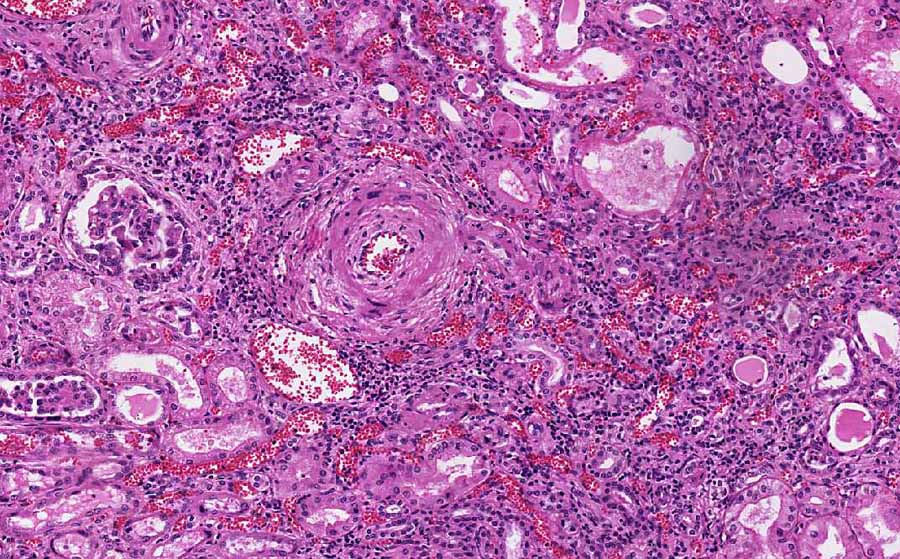

Kidney- Area  2: Note how small is the lumen in this vessel with concentric intimal thickening.

·         Concentric intimal thickening of blood vessels (hyperplastic arteriolitis): There is extensive intimal thickening due to a proliferation of elongated, concentrically arranged smooth muscle cells and layers of concentric collagen. Pale staining substance probably proteoglycans and plasma proteins are also present in these concentric thickenings. Histologically, these vessels resemble the cross section of an onion (onin-skinning of vessels). (Kidney- Area 1 and 2)